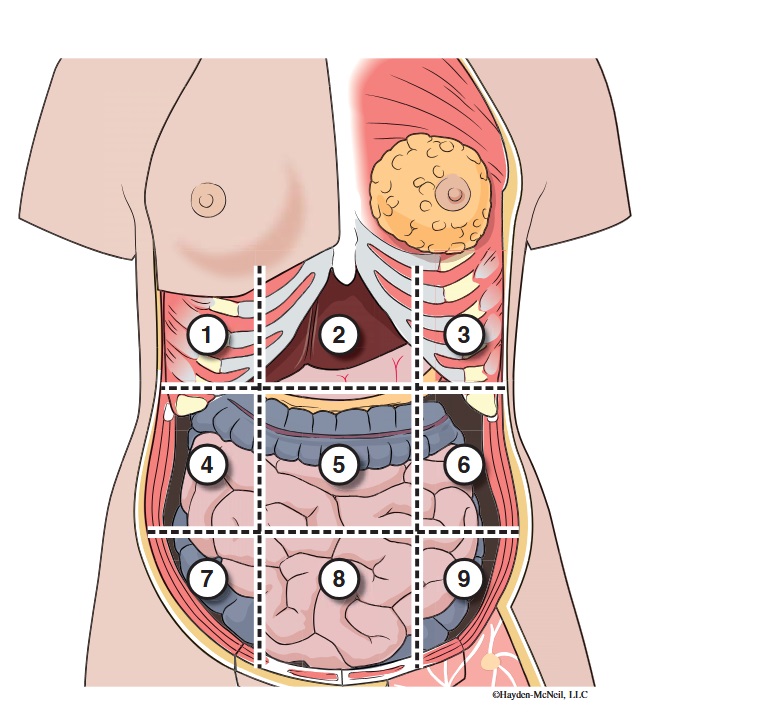

What abdominal region is labeled #1?

right hypochondriac

What abdominal region is labeled #2?

epigastric

What abdominal region is labeled #3?

left hypochondriac

What abdominal region is labeled #4?

right lumbar

What abdominal region is labeled #5?

umbilical

What abdominal region is labeled #6?

left lumbar

What abdominal region is labeled #7?

right iliac/ inguinal

What abdominal region is labeled #8?

hypogastric

What abdominal region is labeled #9?

left illiac/ inguinal

What organs are apart of the right hypochrondriac region?

right lobe of liver, gallbladder, right adrenal gland

What organs are apart of the epigastric region?

pyloric end of stomach, duodenum, pancreas

What organs are apart of the left hypochondriac region?

stomach, spleen, left adrenal gland

What organs are apart of the right lumbar region?

ascending colon, right kidney, portion of small intestine

What organs are apart of the umbilical region?

omentum, mesentery, small intestine

What organs are apart of the left lumbar region?

descending colon, left kidney, portion of the small intestine

What organs are apart of the right iliac/ inguinal region?

cecum of large intestines, appendix, right ovary

What organs are apart of the hypogastric region?

ileum, bladder, uterus

What organs are apart of the left iliac/ inguinal region?

sigmoid colon, left ureter, left ovary